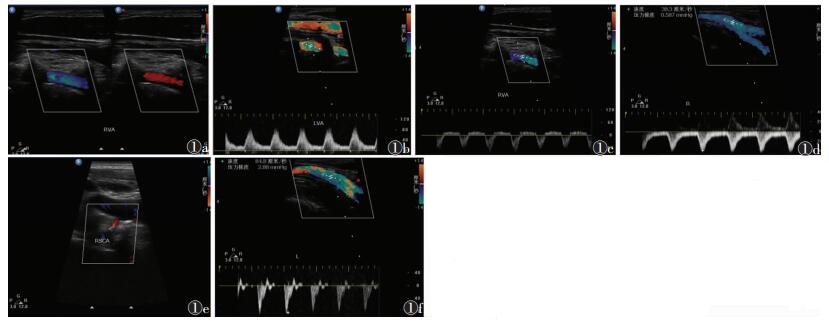

78例中,超声诊断SSS 68例,左侧43例,右侧25例。病因为动脉粥样硬化60例,大动脉炎5例,夹层2例,锁骨下动脉发育不良1例。28例为部分型窃血(图 1),同侧椎动脉频谱显示舒张期为正向血流,收缩期为反向;26例为完全型窃血,椎动脉全心动周期血流为反向;14例为隐匿型窃血,椎动脉收缩期出现切迹;10例超声检查阴性。CDFI示血管狭窄处呈现五彩镶嵌花色血流,频谱呈湍流表现,可见局部血流速度加快,为150~450 cm/s;完全闭塞处未录得血流信号。

图 1 男,67岁,高血压17年,糖尿病6年。颈动脉超声示双侧颈动脉及右侧锁骨下动脉多发粥样硬化斑块形成,右侧锁骨下动脉窃血综合征(部分型);心脏超声示左室后壁增厚,左房偏大 图 1a  右侧椎动脉CDFI,收缩期蓝色舒张期红色双向血流 图 1b  对侧椎动脉代偿性加快的血流频谱 图 1c  右侧椎动脉双向血流异常频谱图像 图 1d  右侧上肢腋动脉舒张期反向血流消失的异常频谱 图 1e  右侧锁骨下动脉起始段粥样硬化斑块致局段管腔狭窄的彩色血流图像 图 1f  对侧上肢腋动脉正常血流频谱图像